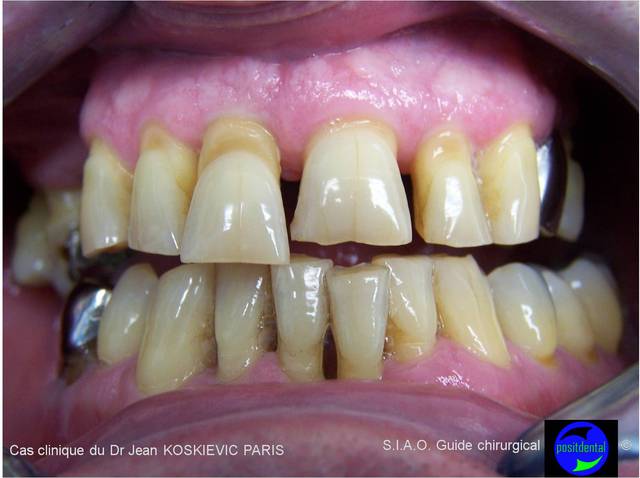

Photo clinique de Posit...

très moyen, aucune profondeur, déformation de l'image(objectif grand angle non adapté au macro dentaire...), couleur non réaliste

Guide +1, photo -1

l'image n'est pas assez net, trop flou au niveau de la canine ce qui signifie que soit l'appareil ne permet de faire la mise au sur une zone donnée que l'on choisit (ici c'est l'appareil qui décide) soit que tu as photographié en priorité l'incisive centrale et non le sujet principal qui est l'incisive latérale...

pas convaincu.